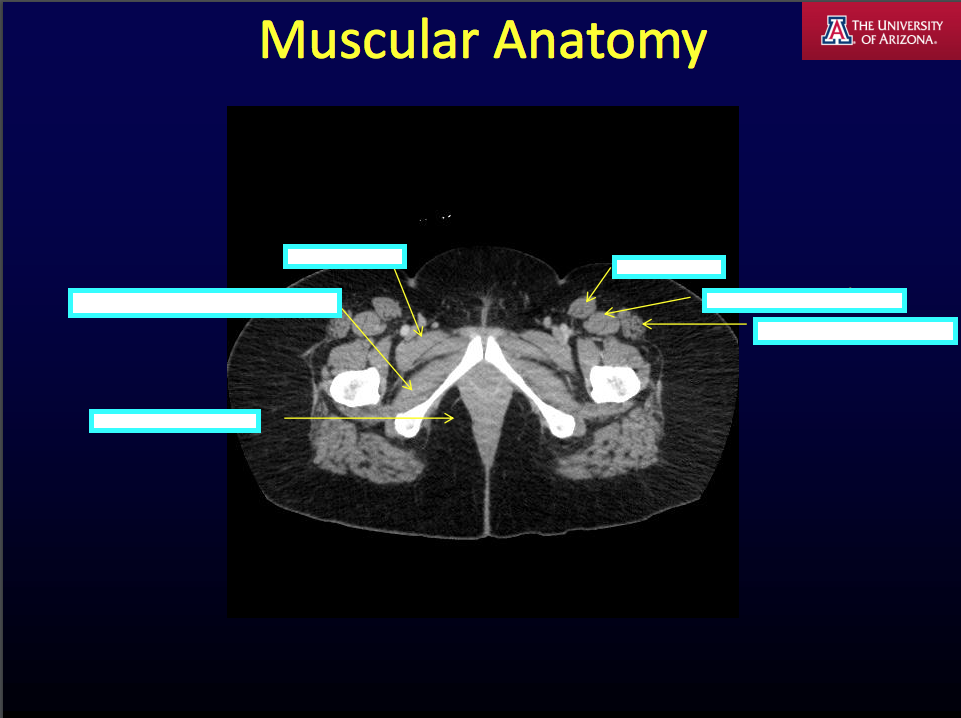

CT